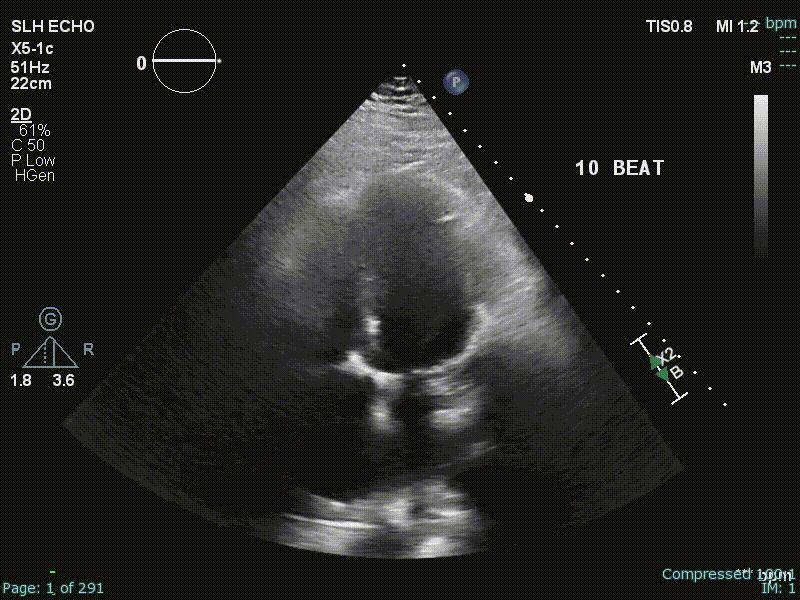

- Echo, CT (with contrast enhancement to assess pericardial inflammation), CMR, Cath

- Specific diagnostic echocardiographic criteria for the diagnosis of constrictive pericarditis has been proposed by the Mayo Clinic and include:

- septal bounce or ventricular septal shift with either medial e′ >8 cm/s or hepatic vein expiratory diastolic reversal ratio >0.78 (sensitivity 87%, specificity 91%; specificity may increase to 97% if all criteria are present with a correspondent decrease of sensitivity to 64%

Echo

“Echo diagnosis of constriction is all about pattern recognition” - Sanjiv Shah

Ventricular Interdependence? Think constriction

Constrictive physiology should be considered when evidence of enhanced interdependence is observed by echocardiography.